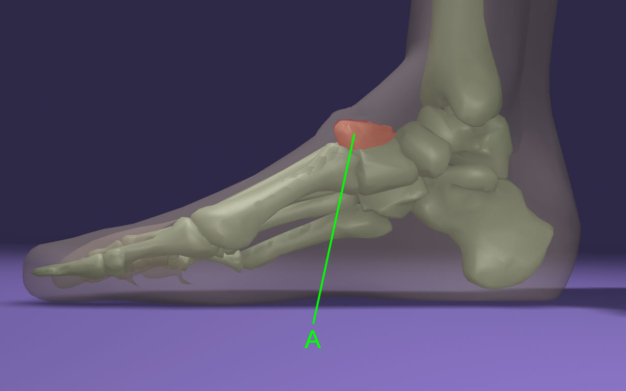

A láb hátoldalán alakulhat ki a „dudor” (A), mely az I-es metatarsus és az I-es ékcsont (Os cuneiforme mediale) között létrejött csontszerű felrakódás.

Többnyire a betegesen túlívelt lábboltozat (pes excavatus, pes cavus) esetében van az, hogy a cipő konfliktusban van a lábbal a láb hátoldalán: nyomja a lábat a cipő fűzője és a cipő más záró elemei.

Ez a lábbetegség egyéb más kellemetlen jelenségekkel jár együtt az alapprobléma (pes excavatus, pes cavus) megléte miatt, ezért a komplex kezelés egy jól formázott ORTFLEX gyógycipővel, benne egy korrigáló EASYINSOLE Custom talpbetéttel megoldható.